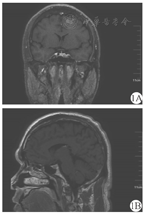

男,32岁,因"面容改变手足发胀4年余,心悸、眼胀3个月余"入院。患者4年前开始出现面容改变,表现为颧骨突出、鼻翼增宽、嘴唇增厚,逐渐出现手足发胀和变大,鞋码由42码渐增大到43码,手指关节增粗,自觉皮肤粗糙,油脂汗液分泌较多。伴多饮、多尿。1年前体检发现甲状腺功能异常,未诊治。入院前3个月出现心悸和眼胀,行甲状腺功能检查,游离三碘甲状腺原氨酸(FT3)7.26 pmol/L(正常值3.28~6.47 pmol/L),促甲状腺激素(TSH)<0.005 mU/L(正常值0.49~4.91 mU/L),促甲状腺素受体抗体(TRAb)2.7 U/L(阳性);甲状腺超声示甲状腺形态饱满,腺体回声粗糙、不均匀,呈网格样改变,甲状腺血流信号丰富,甲状腺弥漫性病变。入院1周前(5月12日)复查甲状腺功能,总三碘甲状腺原氨酸(TT3)3.59 nmol/L(正常值1.01~2.48 nmol/L),总甲状腺素(TT4)141.85 nmo1/L(正常值69.97~152.52 nmol/L),FT3 12.56 pmol/L,游离甲状腺素(FT4)24.44 pmo/L(正常值7.64~16.03 pmol/L),TSH<0.05 mU/L;生长激素3.75 μg/L(正常值0~3 μg/L),IGF-1 545 μg/L(正常值71~234 μg/L)。为明确诊断而收入我科。体格检查:肢端肥大症面容,双眼突出,双侧甲状腺质地软,可闻及血管杂音,触发泌乳阴性,心肺腹查体未见明显异常,双下肢无水肿。入院完善相关检查,TRAb 2.7 U/L(阳性);抗甲状腺球蛋白抗体102.7 kU/L,抗甲状腺过氧化物酶抗体509.16 kU/L;随机生长激素4.05 μg/L;75 g口服葡萄糖抑制生长激素试验0、30、60、120和180 min分别为3.94、3.04、3.12、3.72和4.17 μg/L;超声心动示三尖瓣少量反流,二尖瓣极少量反流(生理性);腹部超声示左肾小囊肿;胸前12导联心电图示窦性心动过速(心率95次/min)。鞍区动态增强MRI示垂体强化不均匀,左侧可见类圆形延迟强化影,直径约7 mm,垂体瘤不除外(图1)。诊断为肢端肥大症垂体生长激素瘤合并Graves病。给予甲巯咪唑(Merck KGaA,国药准字J20171078,商品名:赛治)10 mg口服,1次/d;心率95~100次/min时给予酒石酸美托洛尔[阿斯利康药业(中国)有限公司,国药准字H32025390]12.5 mg口服,2次/d。治疗约40 d后(6月27日),TT3 0.93 nmol/L,TT4 62.04 nmol/L,FT3 4.86 pmol/L,FT4 9.28 pmol/L,恢复至正常水平;但是TSH仍<0.05 mU/L,继续口服原剂量甲巯咪唑治疗。8月8日复查甲状腺功能,TSH 5.23 mU/L,恢复正常;但复查肝功能示转氨酶升高,甲巯咪唑减量至5 mg/次,1次/d。10月3日复查甲状腺功能,结果均正常,甲巯咪唑继续减量至2.5 mg/次,1次/d;11月13日调整为2.5 mg隔日1次,此时患者眼胀等症状缓解。另一方面,患者生长激素和IGF-1水平均明显升高,进一步行口服葡萄糖抑制试验,结果示各时间点生长激素不能被抑制到1 μg/L以下,提示生长激素自主分泌;鞍区动态增强MRI示垂体左侧延迟强化,垂体瘤不除外。手术切除是肢端肥大症的一线治疗方法,神经外科会诊后建议控制甲状腺功能后择期手术,故暂给予患者醋酸奥曲肽微球(进口药品注册标准JX20050124,Novartis Pharma Schweiz AG)20 mg深部肌内注射以抑制生长激素分泌,约28 d注射1次。治疗后约1个月,生长激素0.88 μg/L,IGF-1 247 μg/L,明显下降。该患者出院后随访6个月,每个月复查甲状腺功能、血常规、肝功能、生长激素和IGF-1等,基本正常。患者除初次注射48 h出现一过性腹泻,未出现腹痛和注射部位不适等不良反应,未因药物的不良反应停药。

注:冠状位(1A)和矢状位(1B)动态增强MRI示鞍底局部下陷,垂体饱满,左侧可见类圆形延迟强化影,直径约7 mm